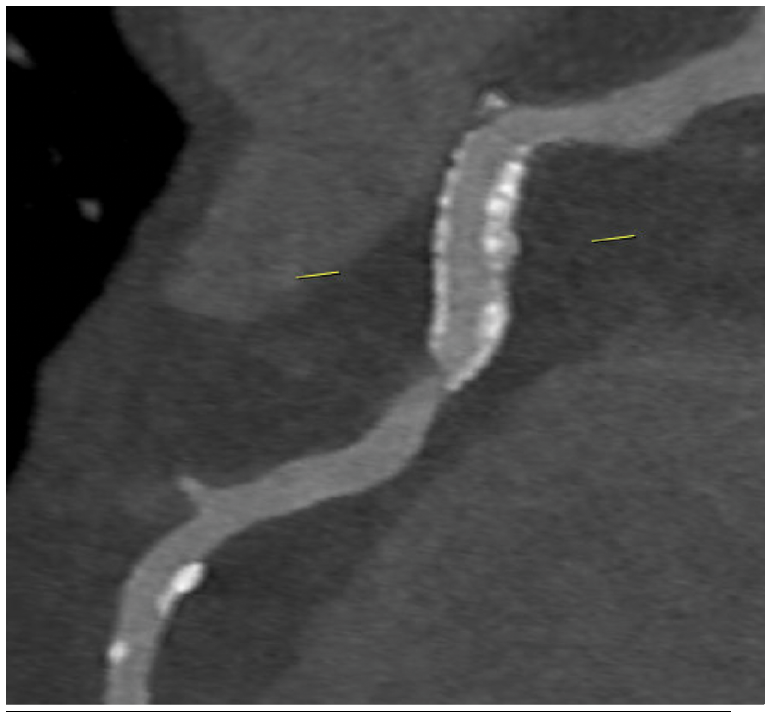

Images/courtesy WellSpan Heart & Vascular Institute

The RCA (Figure 2) demonstrated a patent stent but severe stenosis in the native artery (Figure 3) at the stent’s distal segment. Severe stenosis was noted in the Cx (Figure 4) proximal to the previously placed stent. CCTA findings were confirmed by invasive angiography. A diastolic hyperemia-free ratio (DFR) across the lesion in the LAD was abnormal at 0.89. The patient later received intravascular ultrasound-guided PCI of the Cx, LAD, and RCA.